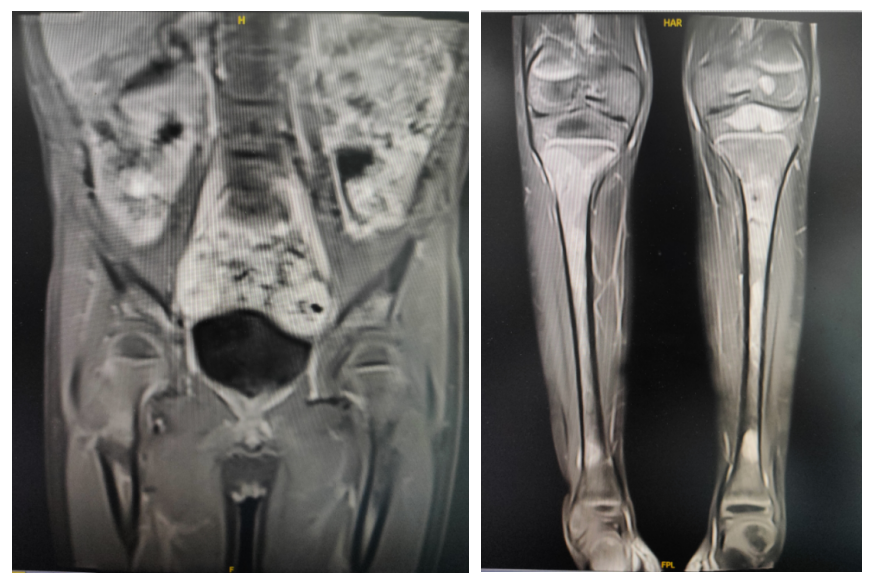

维持治疗与随访: 患者2023年5月开始西达本胺+依托泊苷治疗;2024年停依托泊苷,口服西达本胺单药治疗。每三个月定期复查,末次复查2025年10月16日疾病(淋巴结和骨病灶)呈持续稳定状态,患儿服药耐受可,无不适症状。

2024-11复查MR提示病灶稳定